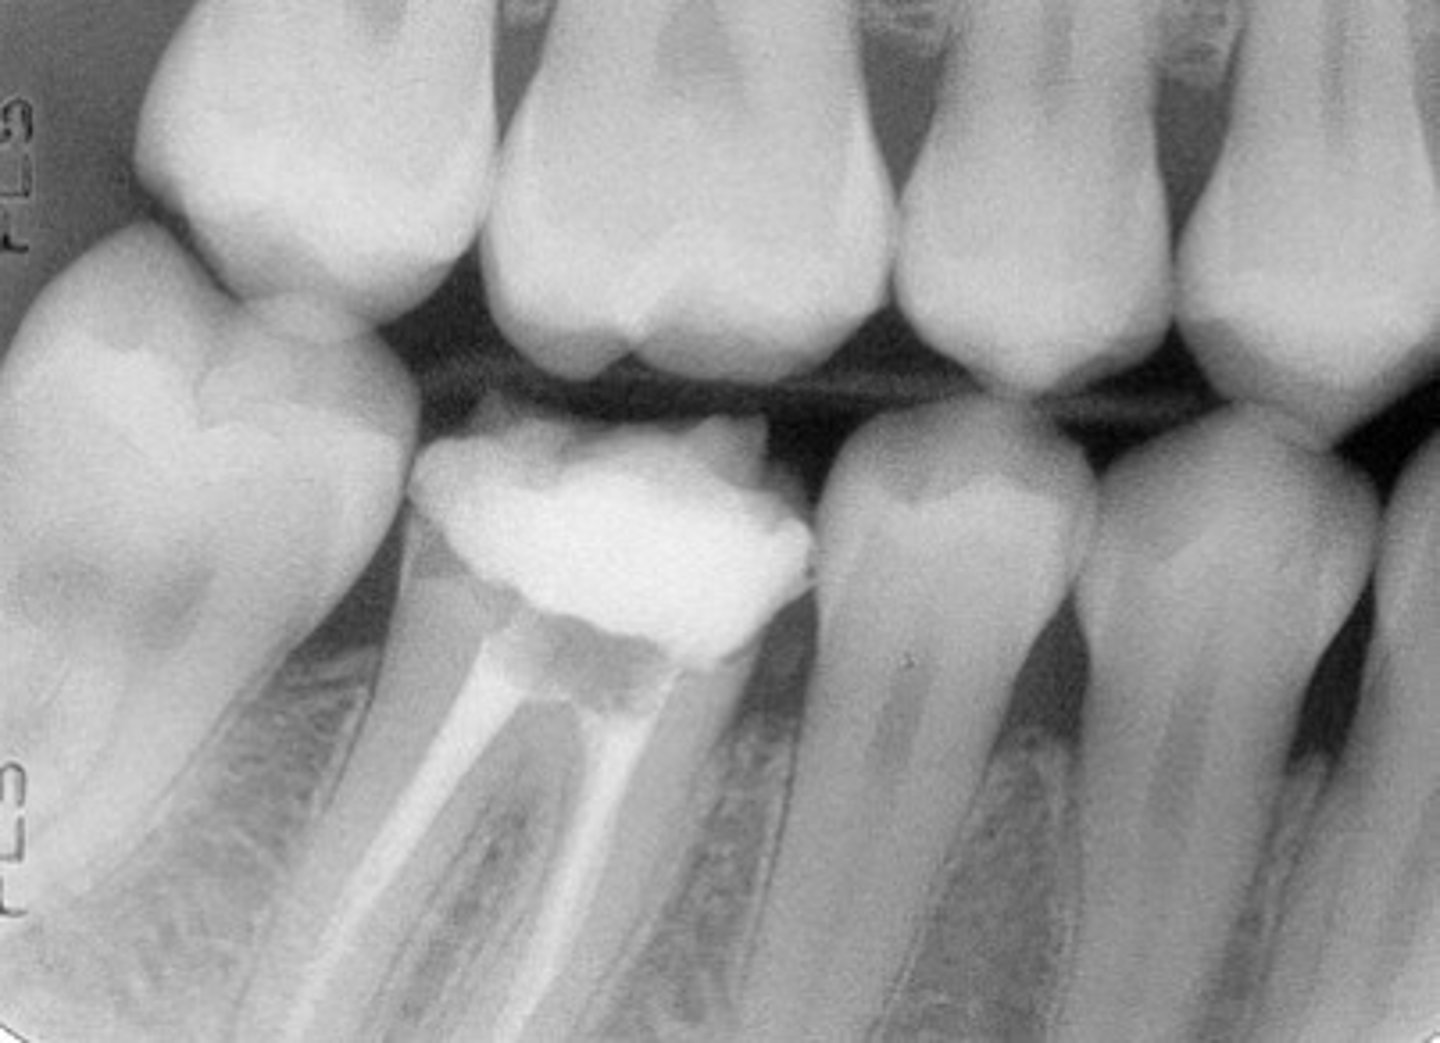

Bitewing radiograph

image view showing the crowns of both arches on one film

bitewing radiographs used to detect:

or monitor interproximal caries if the proximal surfaces of the teeth cannot be visually tactilely examined